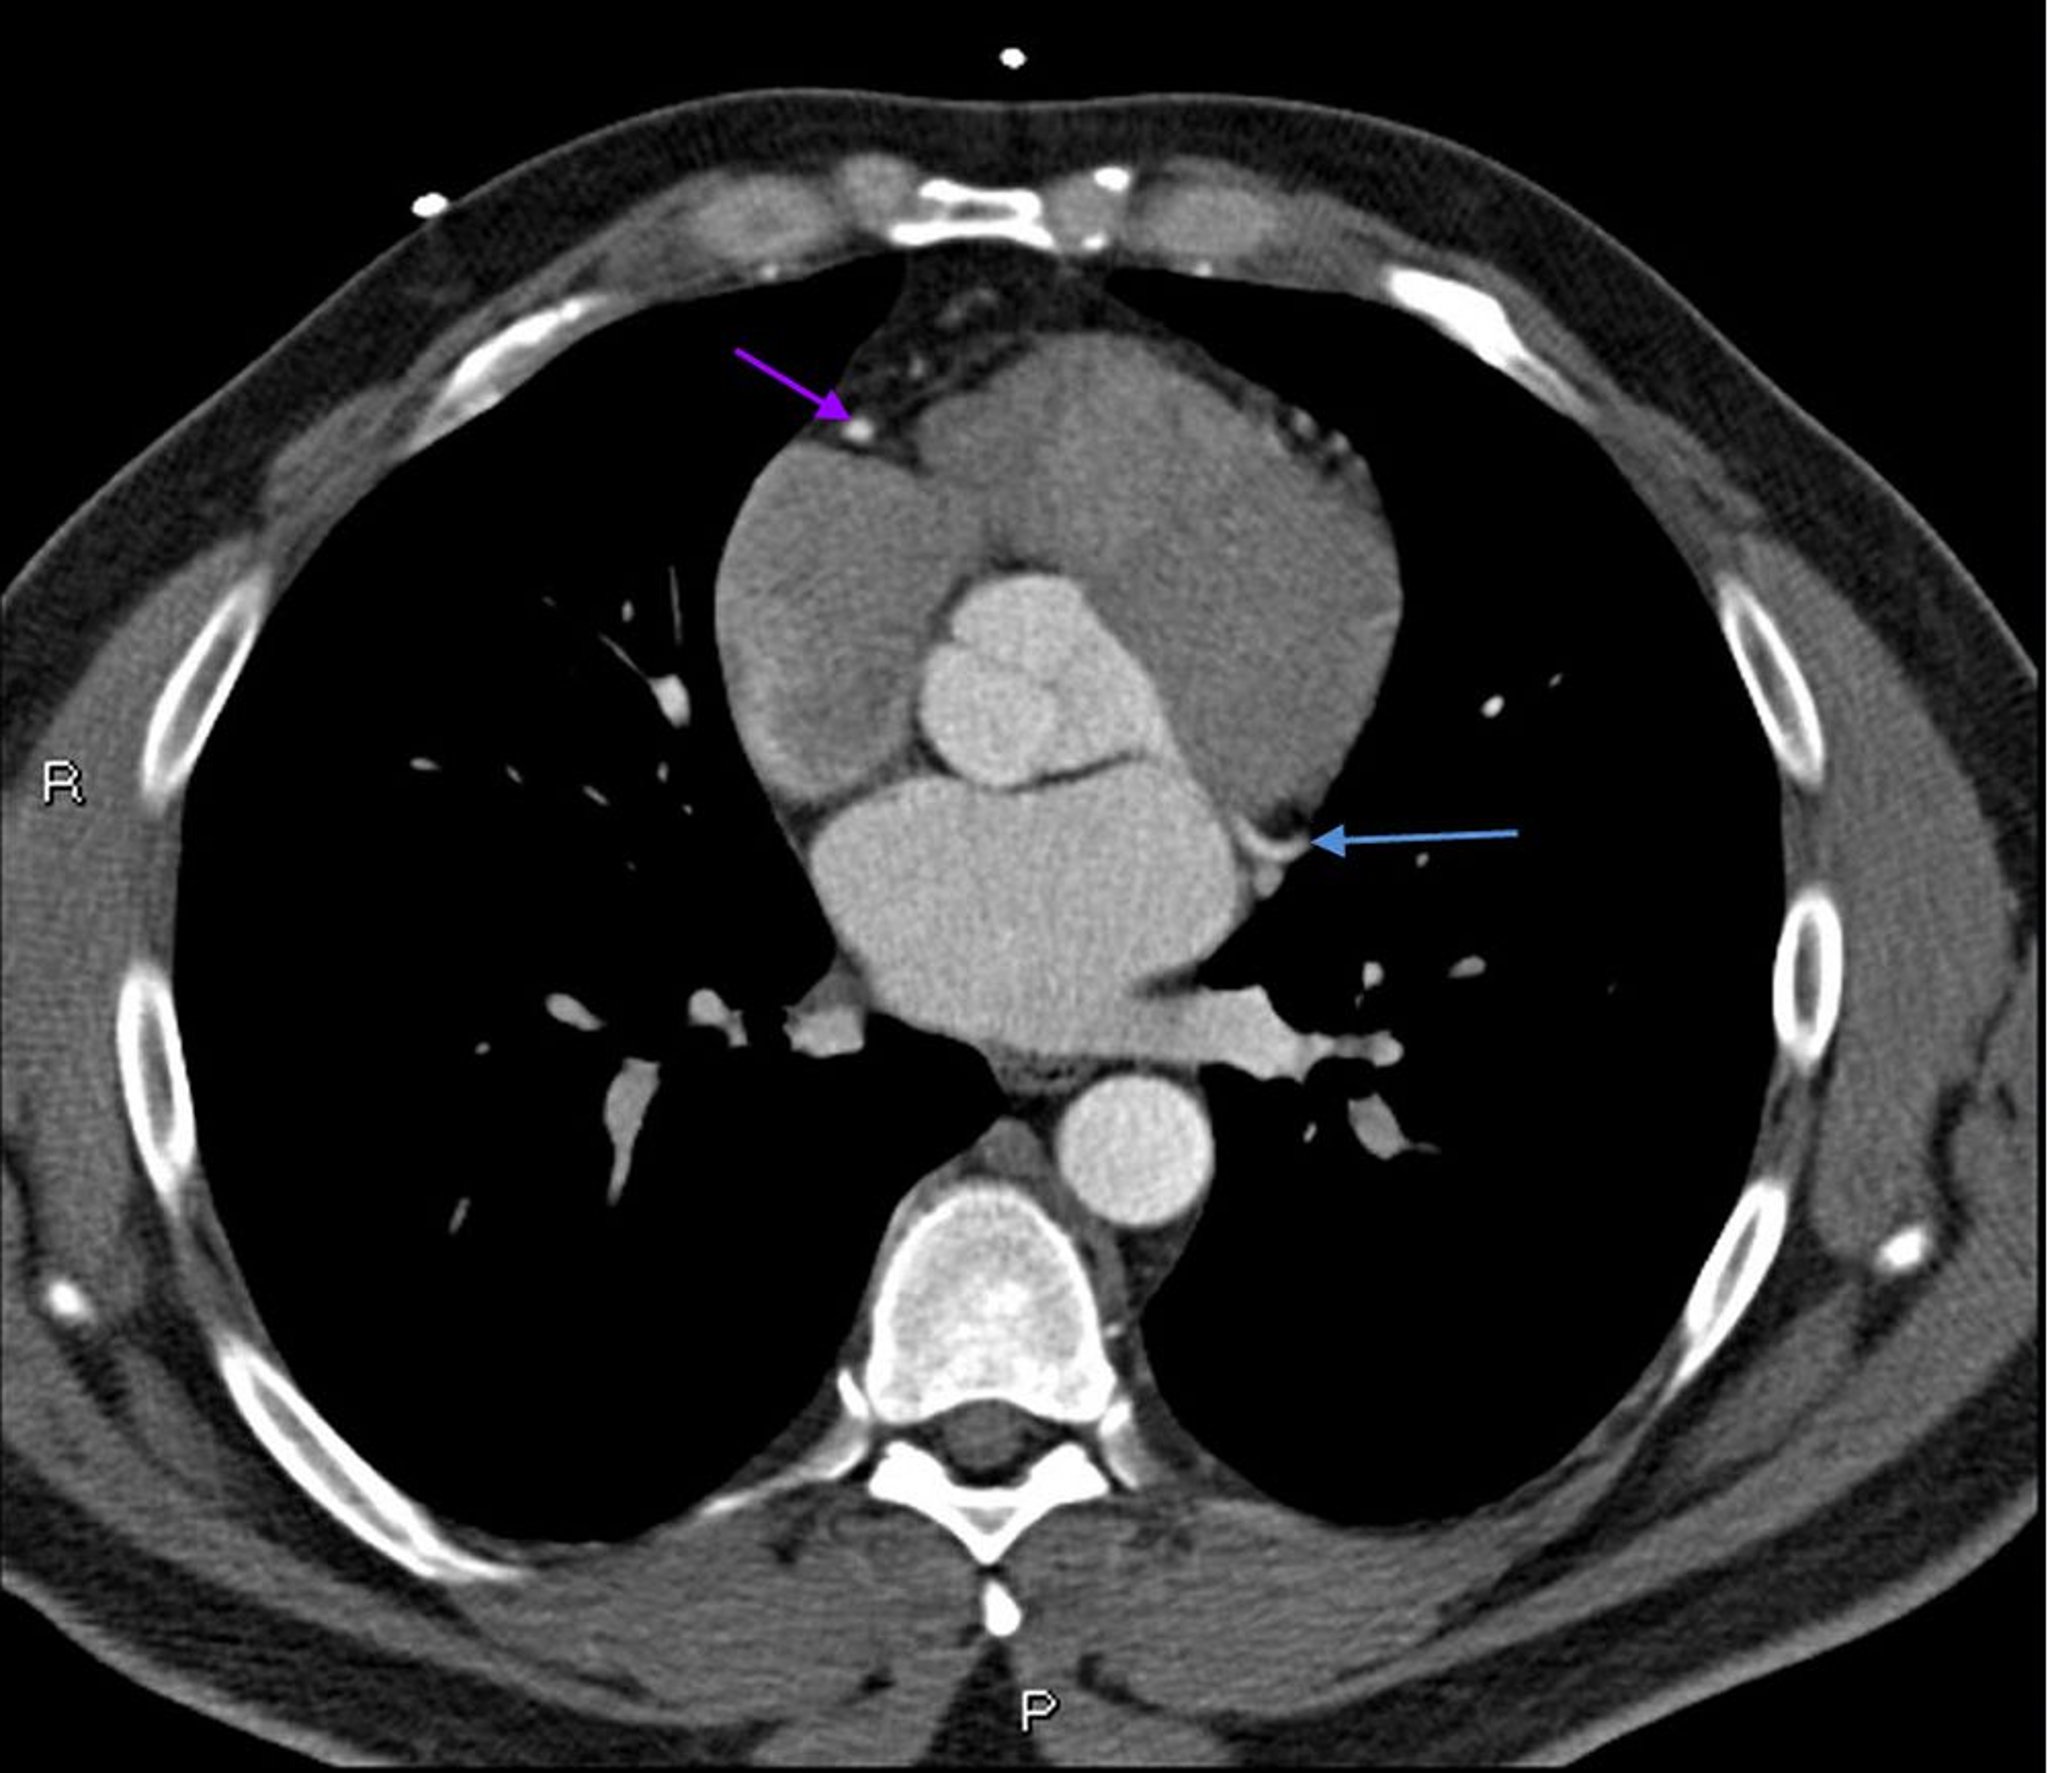

Phim chụp CT có thuốc cản quang cho thấy các động mạch vành bình thường – Lát cắt 6

Phim chụp CT có thuốc cản quang này cho thấy các động mạch vành bình thường. Động mạch chính bên trái được biểu thị bằng mũi tên màu đỏ. Động mạch vành xuống trước trái và động mạch mũ trái lần lượt được biểu thị bằng mũi tên xanh lá cây và xanh lam và động mạch vành phải được biểu thị bằng mũi tên màu tím.